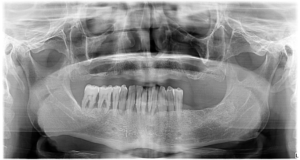

În radiografia prezentată mai jos puteţi observa situaţia dentară iniţială a pacientului nostru, dar şi rezultatul obţinut după inserarea implanturilor convenţionale.

În timpul intervenției am extras, de asemenea, și dinții de la nivelul mandibulei deoarece erau extrem de afectați să îi puteau provoca probleme de sănătate în viitor.